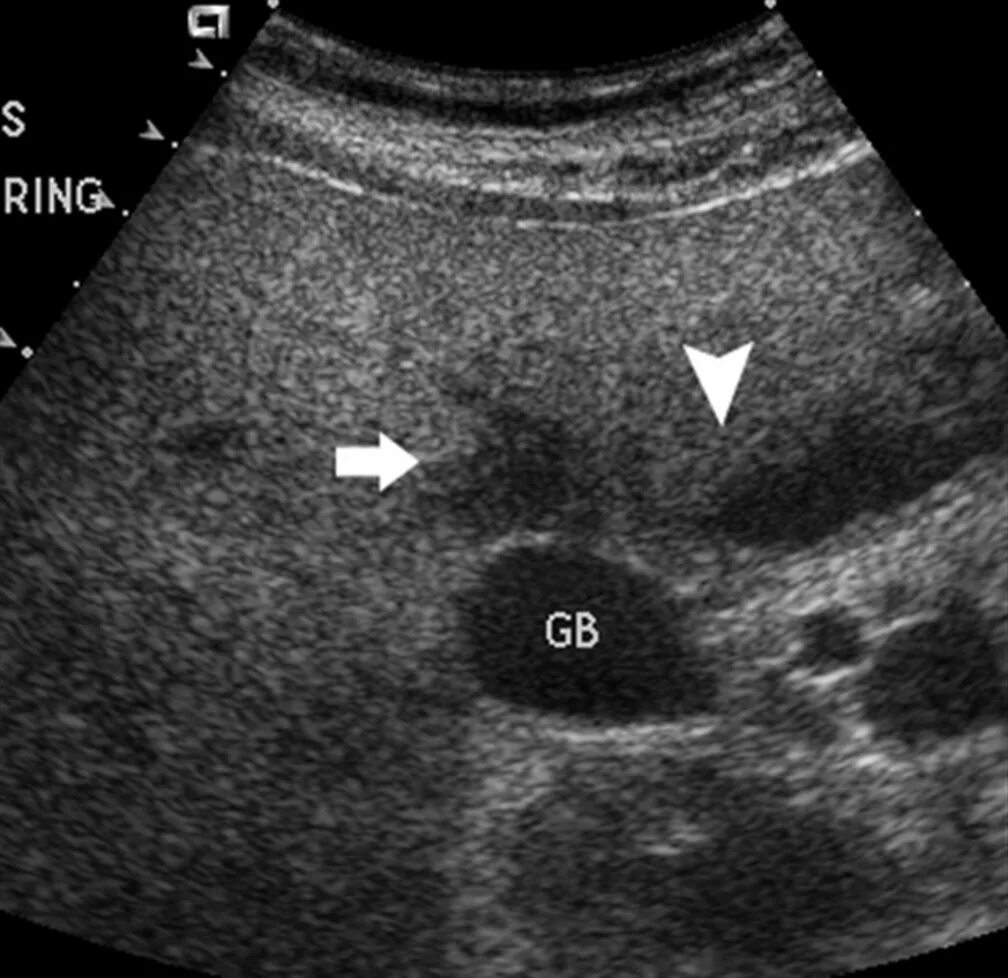

Очаги регенерации